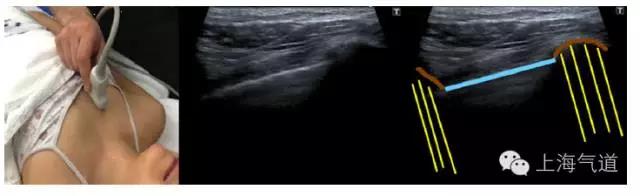

图7探头置于上胸部锁骨中线肋间隙处取纵切面,棕色为上下肋骨成像,并在后方形成了伪影(黄色),蓝色为胸膜(壁层和脏层)形成的高亮回声线,可伴随呼吸动作轻微移动(即胸膜滑动征)